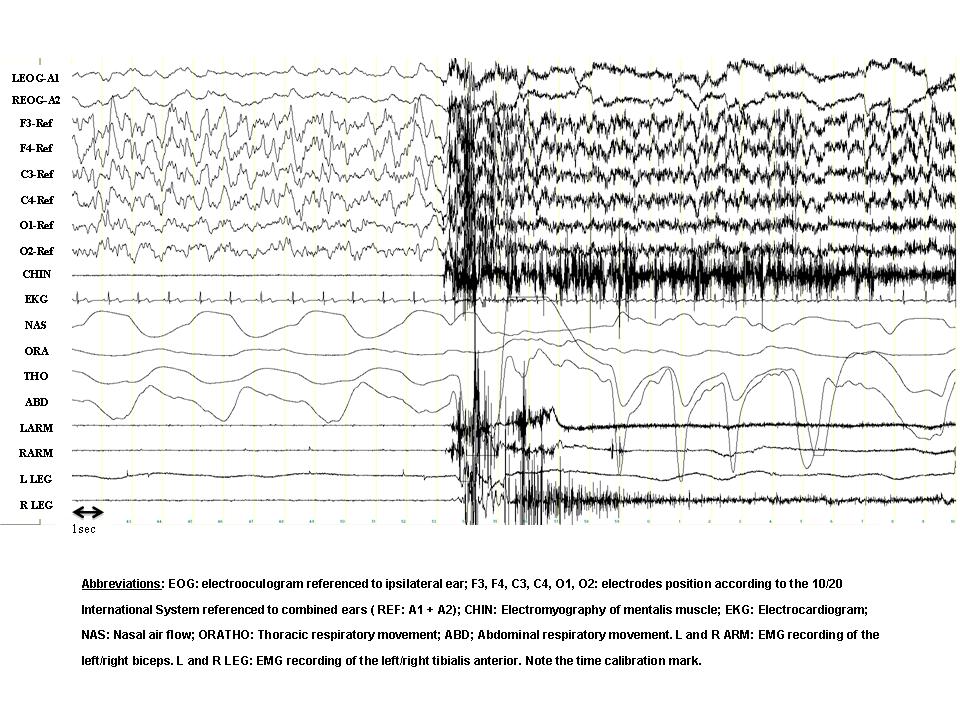

A 23-year-old female complained of abnormal behaviors during sleep that began at the age of 6 years. The episodes appeared within the first 1-2 hours of sleep and were relatively frequent (7-15 per month). She often recalled dreaming during the episodes. Typical dream contents were that she was locked in a hole without air or that she had been buried alive and she strongly needed to escape. Her bed partner referred that the episodes often began with the patient immediately leaving the bed, running and opening doors or windows with her eyes open, without awakening. The patient would have partial recall (“fragments”) or no recall at all of the episodes. A nocturnal polysomnographic (PSG) recording after 38 hours of sleep deprivation was performed and the panel shows a 30-second epoch containing one of the events.

- Stage N3.

- There is a sudden awakening directly from stage N3. In the occipital derivations (small arrows) the slow activity decreases in amplitude. In the frontal channels, however, there is persisting delta activity (large arrows), superimposed with EMG artefact. Note the sudden increase in heart rate (arrowheads in the EKG channel). In this particular episode the patient opened her eyes, sat up in bed with fear and spoke unintelligibly. She appeared disoriented and looked around in the room. In a few seconds, however, she relaxed and continued sleeping. The episode can be classified as a confusional arousal.

PSG recordings during the episodes often demonstrate (a) diffuse, rhythmic and synchronous delta activity, most prominent in bilateral anterior regions, or (b) diffuse and irregular moderate-to-high voltage delta and theta activity intermixed with, or superimposed by, alfa and beta activity. This high-amplitude slowing during the event is considered a hallmark of disorders of arousal, although it is non-specific. There is no epileptiform activity or sleep disorder breathing [1, 4].